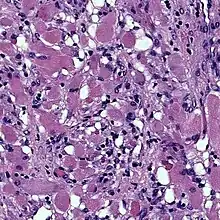

Photomicrograph of fetal-type rhabdomyoma: Note the plump, pink benign skeletal muscle cells.

Cardiac rhabdomyomas are the most common primary tumor of the heart in infants and children. It has an association with tuberous sclerosis.[1] In those with tuberous sclerosis, the tumor may regress and disappear completely, or remain consistent in size.[2] A common histological feature is the presence of spider cells, which are cardiac myocytes with enlarged glycogen vacuoles separated by eosinophilic strands, resembling the legs of a spider.